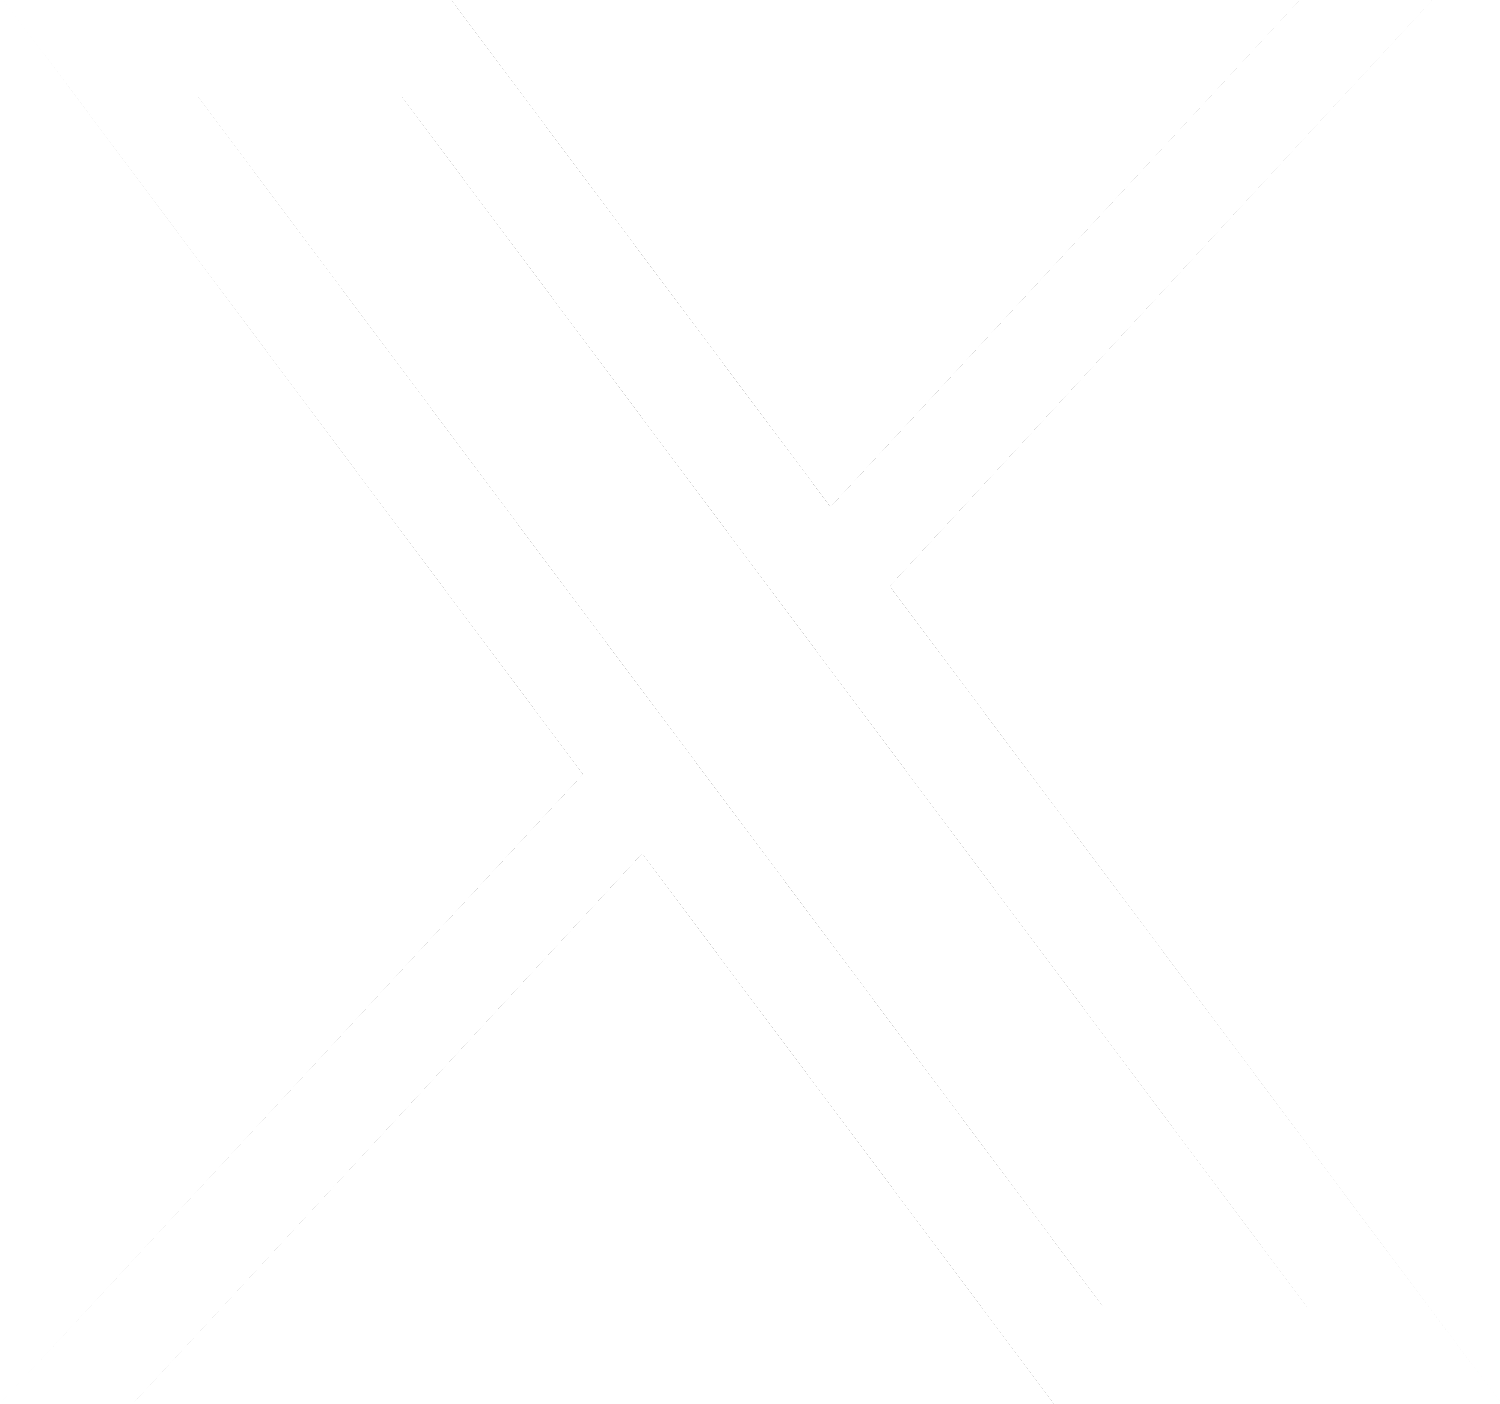

Desconcertados, los médicos realizaron una resonancia magnética a una mujer australiana de 64 años después de que comenzara a sufrir lapsos de memoria y notaron una «lesión atípica» en el frente de su cerebro.

Era una lombriz de ocho centímetros llamada Ophidascaris robertsi, que según investigadores son parásitos comunes en canguros y pitones diamantina pero no en humanos.